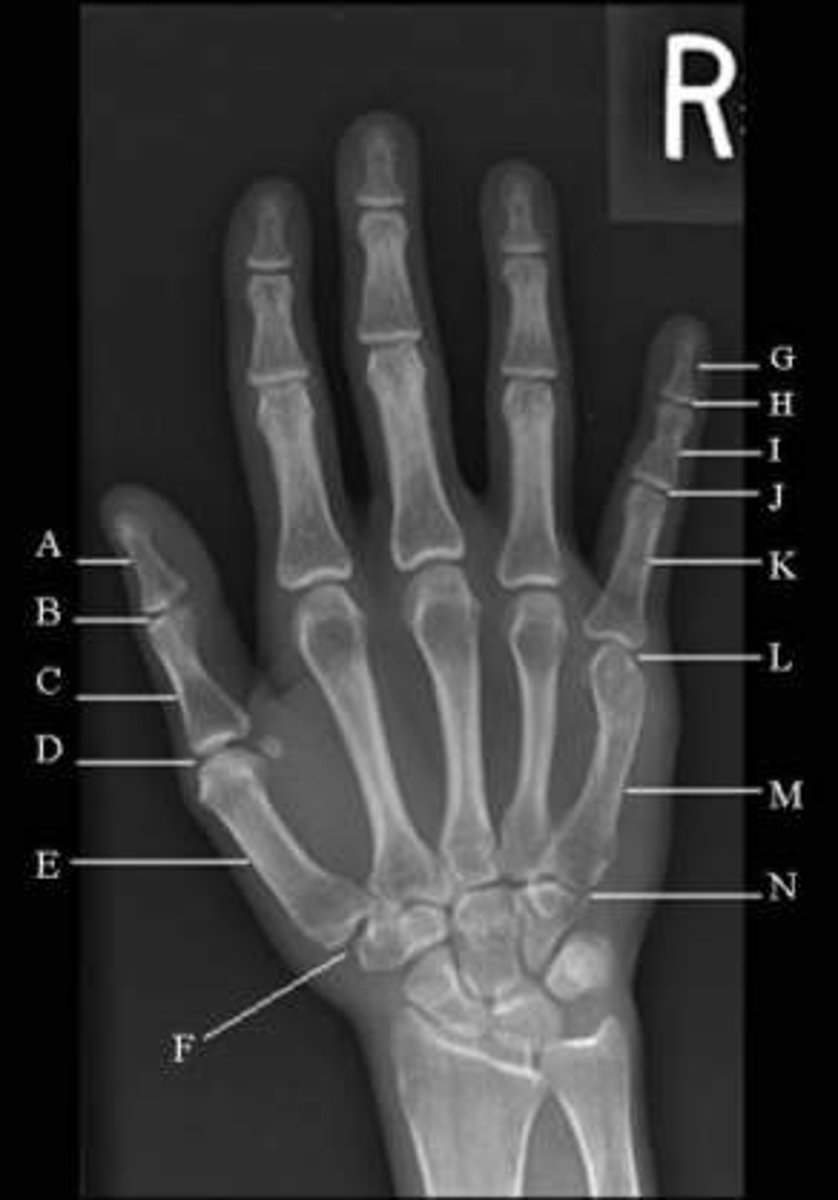

letter N

carpometacarpal joint

letter M

body of metacarpal

letter L

head of metacarpal

letter H

distal interphalangeal joint

Letter I

body of middle phalanx

letter J

proximal interphalangeal joint

letter A

body of distal phalanx

letter B

interphalangeal joint

metacarpophalangeal joint (MCP)

letter D

letter F

carpometacarpal joint (CMC)